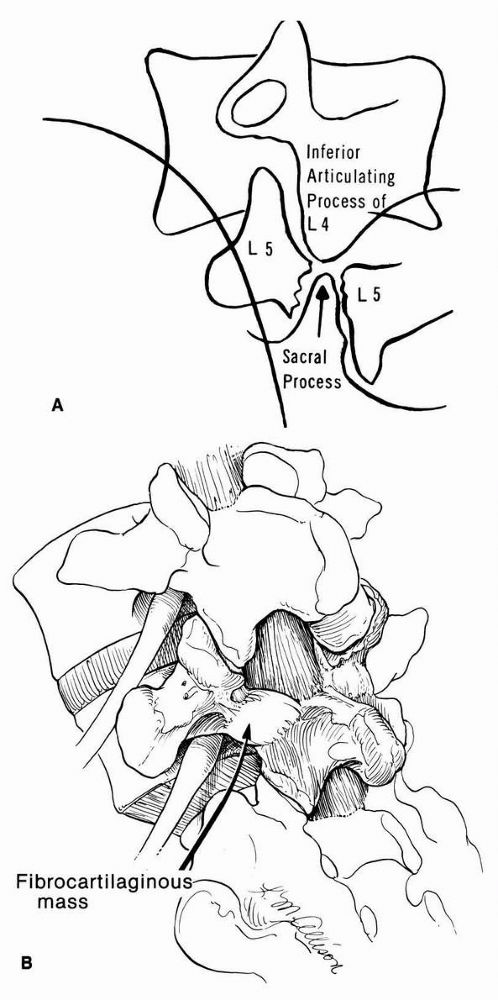

FIGURE 16-23. (A)

Diagram of oblique radiograph of lumbosacral junction, showing cleft in isthmus of the fifth lumbar vertebra. The articular process of the sacrum projects upward and penetrates the cleft, meeting the inferior articular process of the fourth lumbar vertebra. (B) Pathology of spondylolisthesis showing the relation of the nerve root as it courses through the intervertebral foramen. The continuity of the pars interarticularis is bridged at the defect by a fibrous or fibrocartilaginous mass that rarely may encroach on the nerve root of L5. |